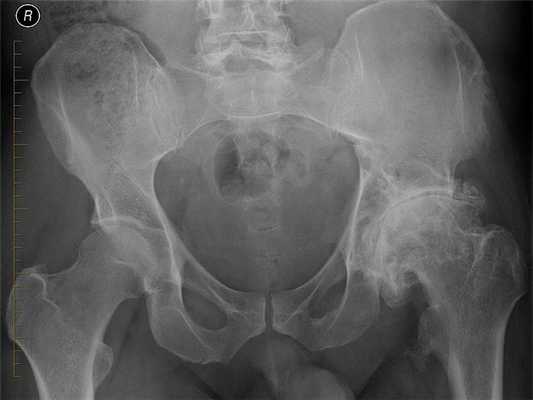

![Рентгенография тазобедренных суставов. Двухсторонний коксартроз: сужение суставной щели, склероз суставных поверхностей.]()

Рентгенография тазобедренных суставов. Двухсторонний коксартроз: сужение суставной щели, склероз суставных поверхностей.